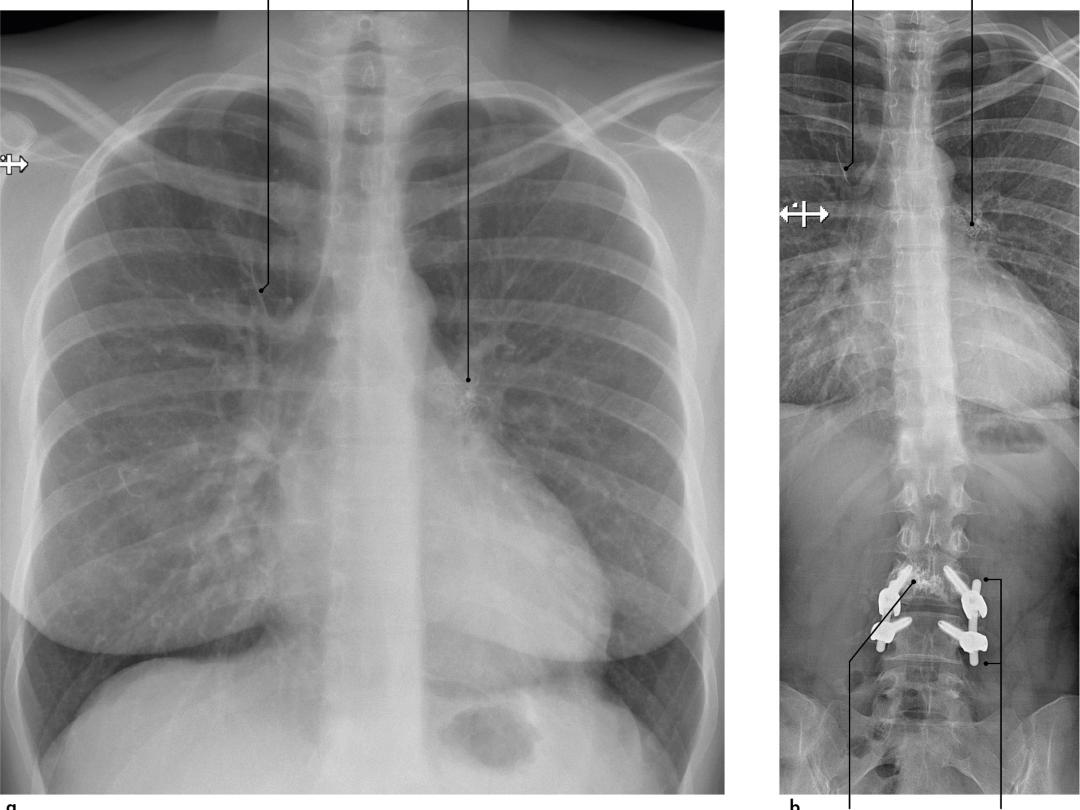

Een 36-jarige vrouw zonder pulmonale voorgeschiedenis kwam bij de huisarts met sinds vijf weken bestaande hoestklachten en dyspneu. Vanwege het vermoeden van een pneumonie kreeg zij een kuur amoxicilline. Omdat de klachten aanhielden, liet de huisarts een X-thorax verrichten (figuur a). Vanwege een afwijkend longbeeld werd de patiënte verwezen naar de polikliniek Longziekten. Aldaar meldde zij behalve hoesten en dyspneu ook thoracale pijn aan de linkerzijde. Bij lichamelijk onderzoek was er geen sprake van tachypneu en waren de longgeluiden niet afwijkend. We vergeleken de thoraxfoto met een röntgenfoto van de wervelkolom die een jaar eerder was verricht (figuur b)…